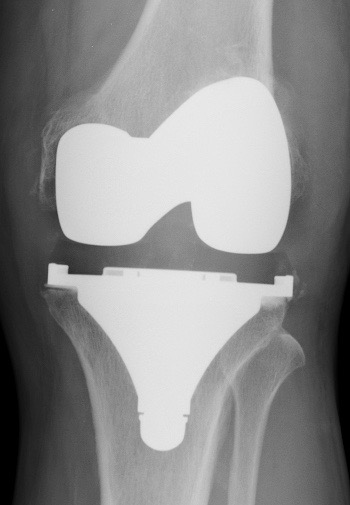

A. PTG à glissement +/- bouton patellaire

le plus couramment utilisé

pour les déformations petites et moyennes

remplace les ligaments croisés

Les ligaments latéraux doivent être en bon état pour assurer une bonne stabilité.